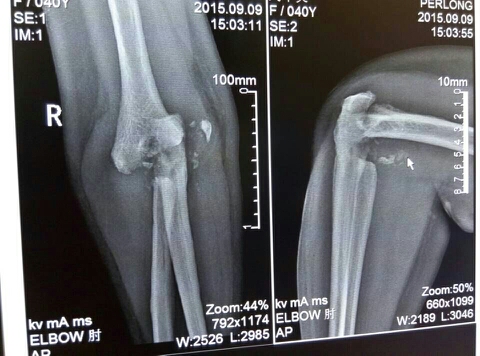

CT51136:无外伤史,进行性疼痛8年。

无外伤史,进行性疼痛8年。

右肘关节神经病性关节病(charcot关节病——即夏科氏关节病)。

建议:行脊髓MRI检查。

右肘关节骨端骨质破坏硬化,且见异位骨化及多发游离小骨片,右肘关节脱位,周围软组织肿胀,结合病史考虑;夏科氏关节病。